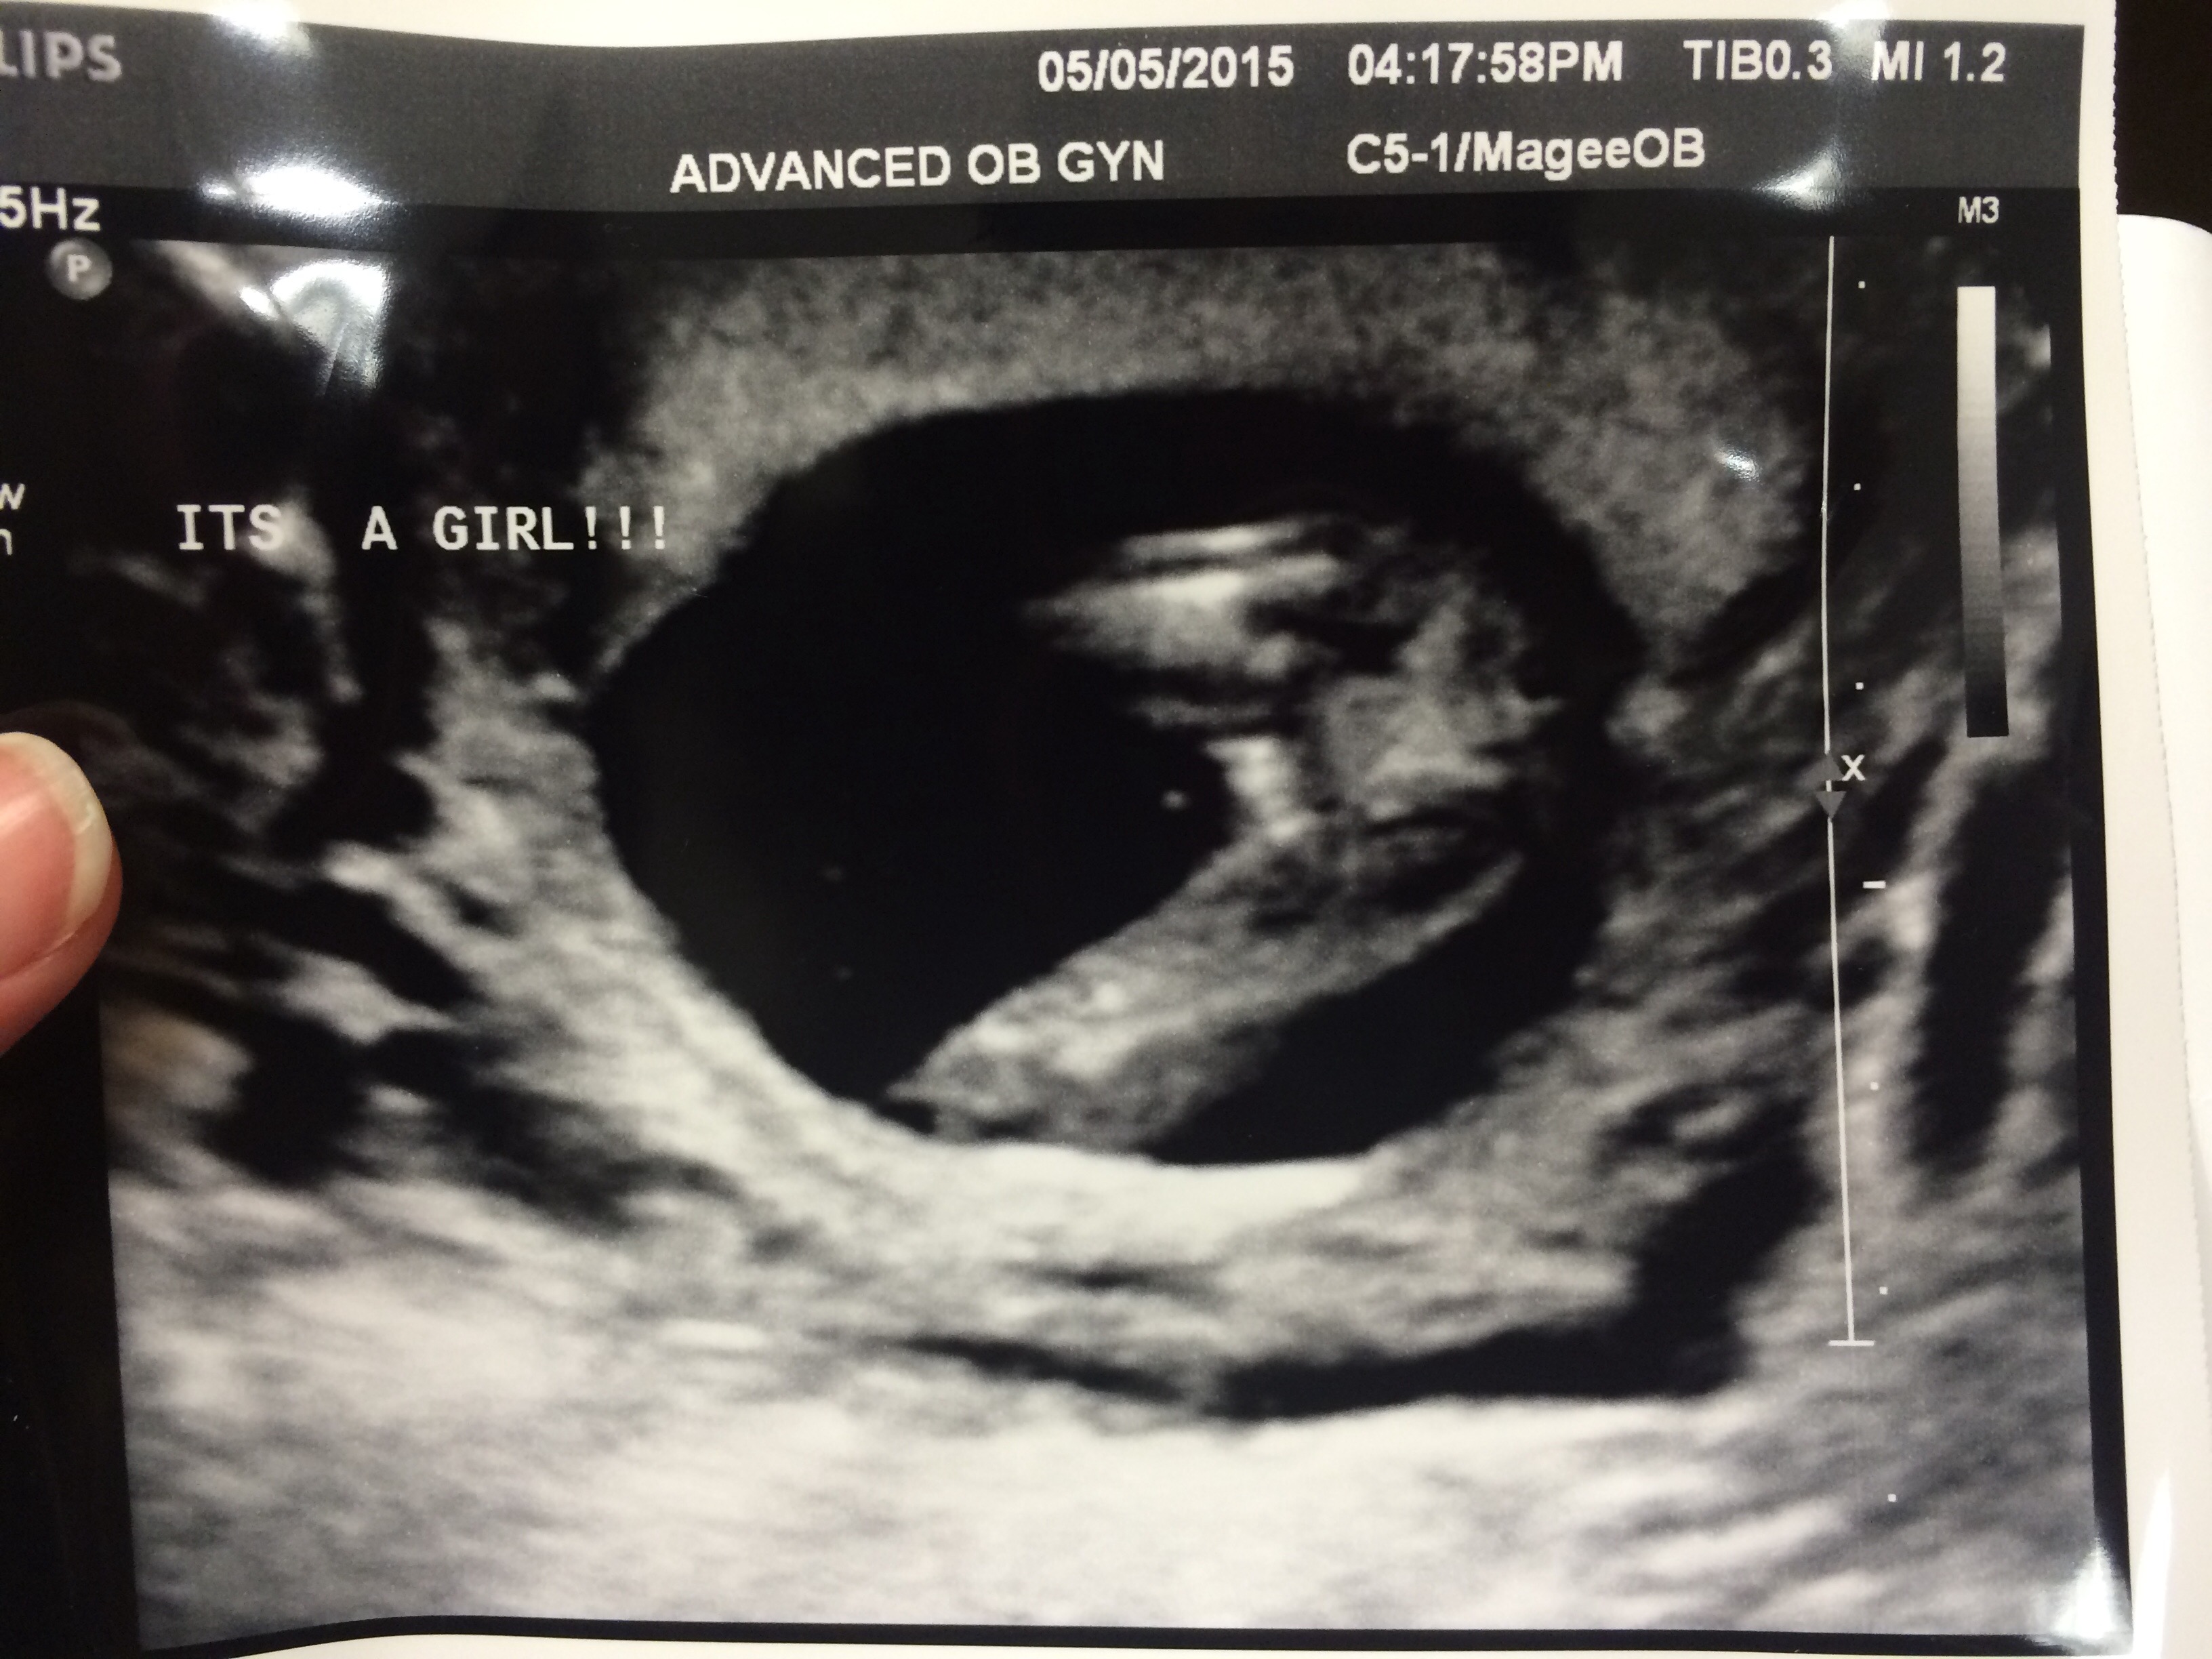

DH and I could care less what this bundle of joy is, but my family is really hoping for a girl since we already have a DS. Just wanted to get some of your opinions. We are announcing on Saturday so I'm sure they will all be thrilled if pink balloons pop out!! Attachment 25109